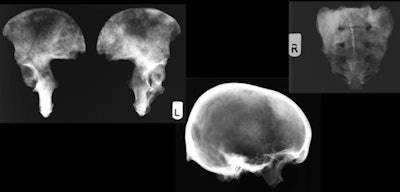

Photos show a 59-year-old male from St. Bride's, with osteoblastic lesions throughout the skeleton, suggestive of prostate cancer. All images and photos courtesy of Katherine van Schaik et al.An interdisciplinary research group from Harvard, London, and Zurich sought to assess differences between osteological and radiological analysis techniques used on bioarcheological samples, and also to understand the effect that radiological analysis might have on establishing levels of ill health in both past and present populations.

X-ray images of the 59-year-old male in the photos above.The study revealed significant differences in the types of lesions that the two analytical methods identified, in the number of lesions found, and in lesion numbers between the sexes.

So how did the individuals found in the crypt live and die? In general, the population of 19th century London was more malnourished than Western European populations today -- many of the St. Bride's skeletons showed evidence of rickets and there were also a few cases of tertiary syphilis. Notably, a subset of the individuals lived into their 70s, and did so seemingly in relatively good health. In at least two cases, evidence of metastatic cancer was noted on the skeletons. X-rays helped to characterize the extent of these lesions.